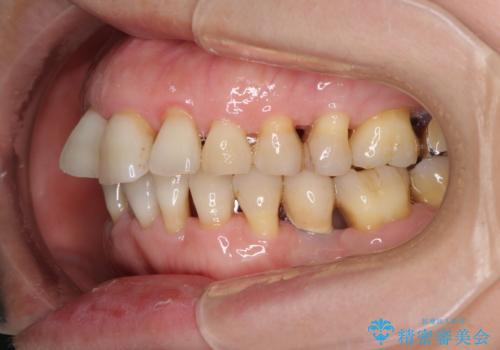

- 近医にてインプラント治療を行った後に矯正治療を希望され、来院された患者様です。

口元の突出感とデコボコが気になっているとのことでしたが、インプラントが既に3本埋入されていたため、抜歯矯正による口元を引っ込めることができない状況でした。

近医での歯周病治療の影響でブラックトライアングルが発現していたため、IPR(歯と歯の間を削る)で隙間を改善しつつ、インプラントを固定源に歯列全体を後方へ移動させることとしました。